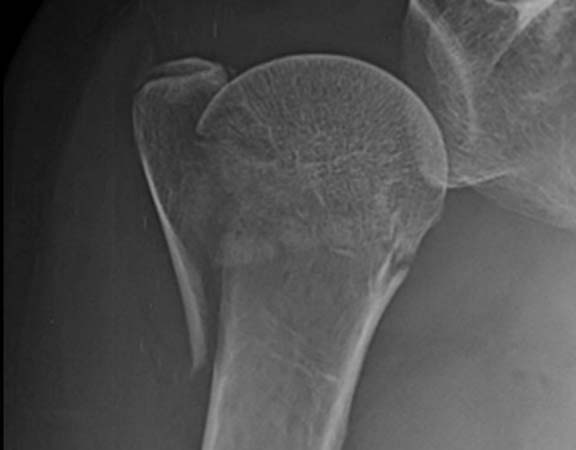

FRATURAS DO OMBRO

As fraturas do úmero proximal acontecem basicamente em 2 perfis de paciente: em jovens após acidente de alta energia, principalmente queda de moto, e outra, no paciente acima de 50 anos, que simplesmente caem, frequentemente relacionada ao osso com osteoporose. Dor no ombro, impossibilidade de mexer e hematoma. Este último pode se espalhar pelo peito e braço Após a avaliação médica, no serviço de emergência, exame de raio-X será solicitado. Algumas vezes a tomografia computadorizada esclarece detalhes quando a fratura é complexa. Ressonância magnética é solicitada nos casos em que a suspeita de fratura é grande, porém o exame radiológico é normal. São os casos de fraturas ocultas. O tratamento para a maior parte dessas fraturas é com tipóia. Repouso do membro acometido por aproximadamente 45 dias é suficiente para a consolidação do osso. A cirurgia é realizada para aqueles pacientes que apresentam grande desalinhamento dos fragmentos da fratura, fraturas dentro da articulação e fraturas com luxações. O principal meio de fixação é com placa e parafusos. Algumas vezes, dependendo do tipo de fratura e idade do paciente, é necessário substituir a região fraturada por uma prótese.